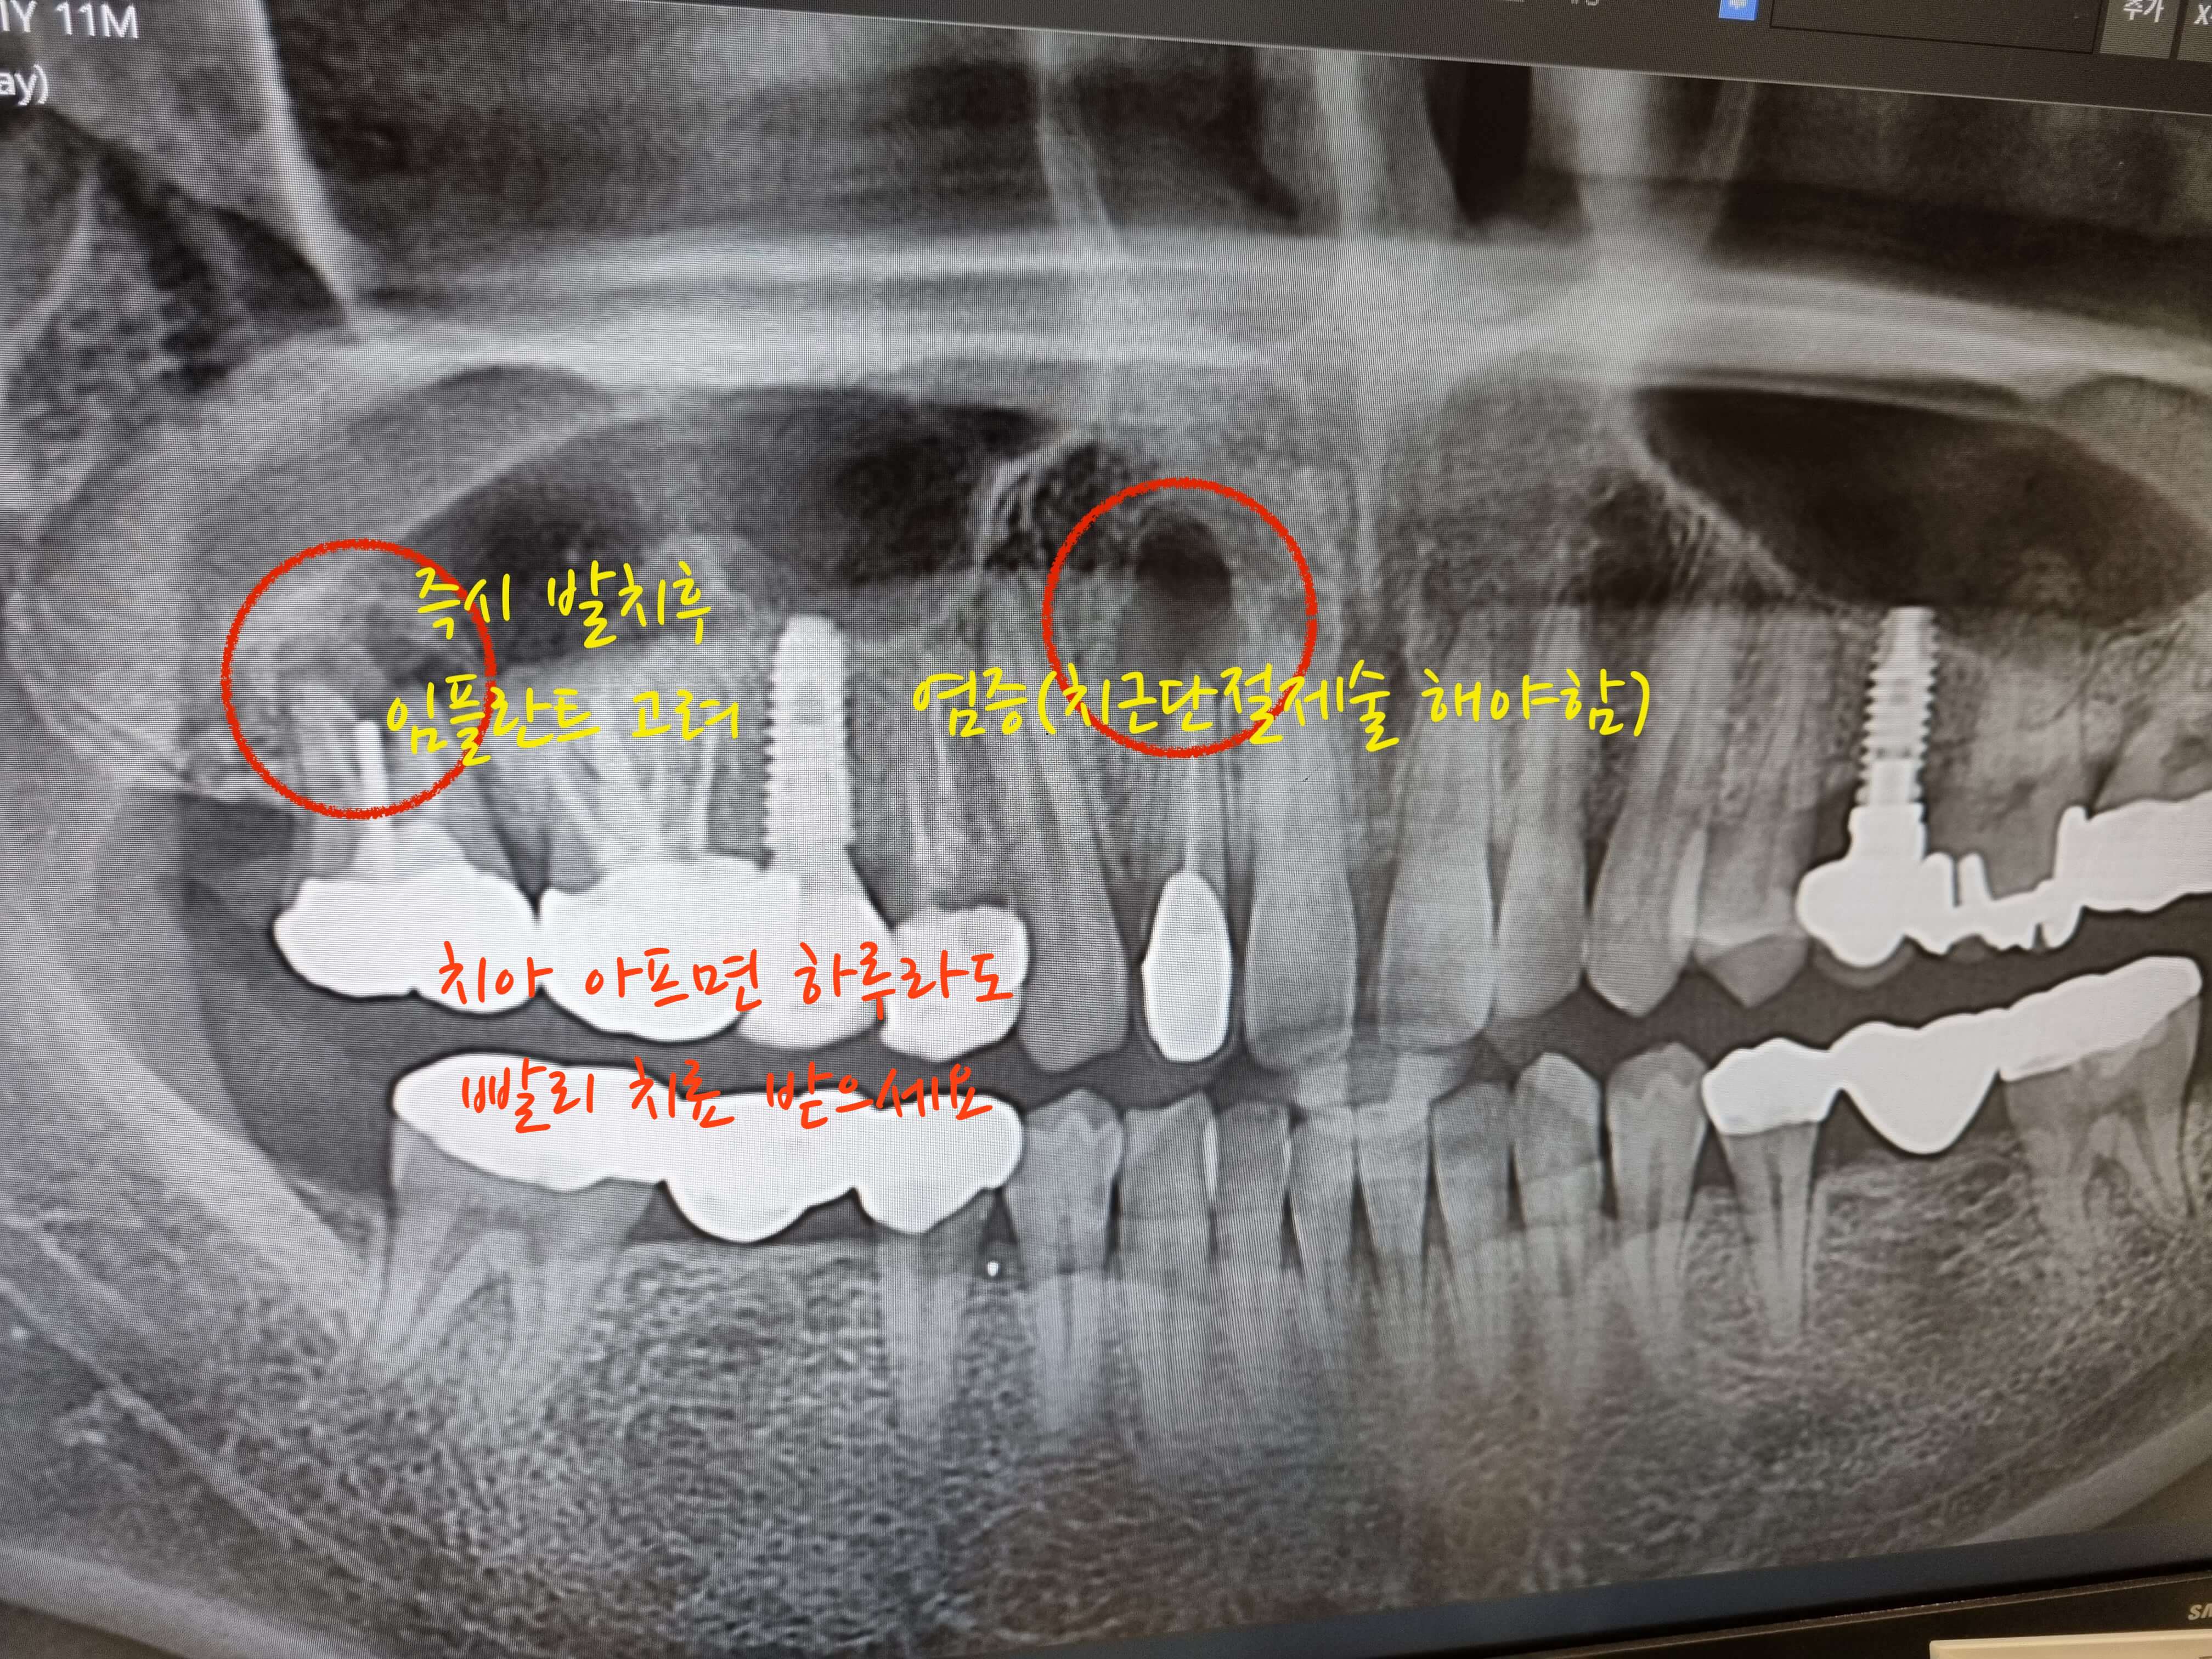

우려하던 일이 발생하게 되었습니다. 이전에 씌어놓은 앞니 크라운 치아 뿌리에서 큰염증이 발견되었고, 맨안쪽 크라운을 씌어놓은 어금니에도 염증이 생겨서 결국 어금니는 발치하고, 앞니 염증 치아는 치근단절제술과 함께 뼈이식을 하게 되었습니다. 이에따른 비용과 후기를 공유합니다.

예전에 신경치료후 크라운을 씌어놓은 맨안쪽 어금니에 뜨거운 물을 마시면 통증이 느껴져서, 기존의 치과를 가서 통증이 느껴진다고 해도 괜찮다고 하여, 신뢰가 가지 않아 새로운 치과에가서 치아 전체를 점검해본결과 2개의 염증이 발견되었습니다.

두이빨모두 신경치료를 마친 크라운을 씌어놓은 치아 인데, 하나는 맨안쪽 어금니이고 나머지는 앞니 치아 입니다. 맨안쪽 어금니는 그날 바로 발치를 하였고, 앞니 같은경우 너무 오래 나두어서 염증이 주변 뼈를 많이 녹여놔서 단계별로 치료하기로 했습니다.